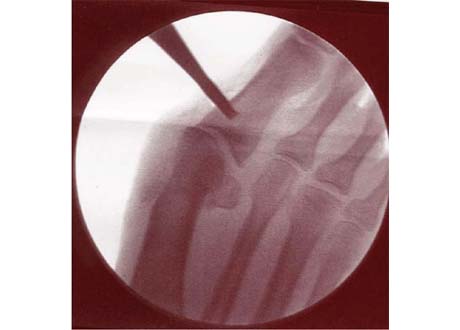

Figure 1

Positioning of the left foot for Minimally Invasibe Surgery (MIS) under Xray guidance